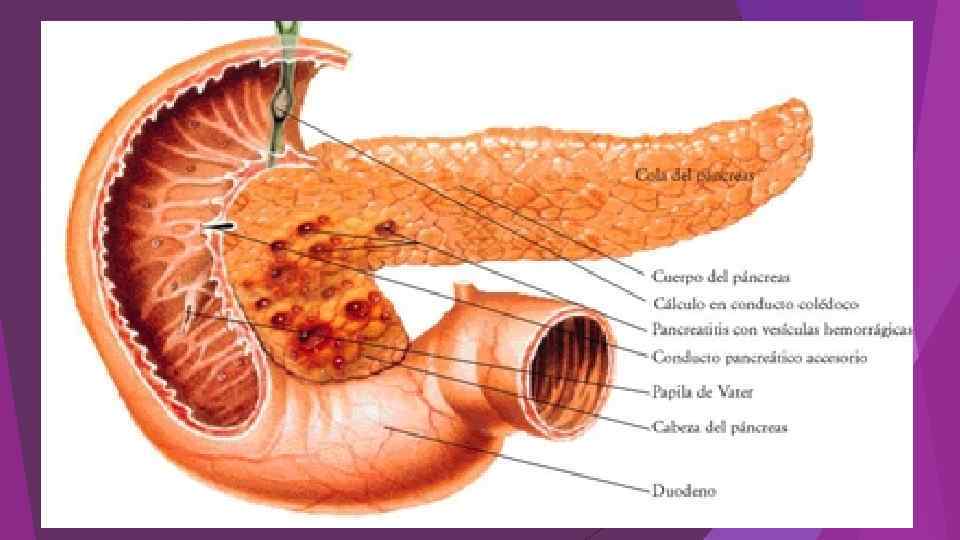

Острый панкреатит – это воспалительно-некротическое поражение поджелудочной железы, в основе которого лежат процессы ферментного аутолиза ( «самопереваривания» ) панкреатоцитов с последующим развитием некроза, дегенерации железы и возможным присоединением вторичной инфекции. Клиническая классификация острого панкреатита 1. Отечный (интерстициальный) панкреатит. 2. Некротический (панкреонекроз) стерильный панкреатит : по характеру некротического поражения: жировой, геморрагический, смешанный; по распространенности поражения: мелкоочаговый, крупноочаговый, субтотальный, тотальный; по локализации: с поражением головки, тела, хвоста, всех отделов поджелудочной железы. 3. Некротический (панкреонекроз) инфицированный панкреатит.

Острый панкреатит – это воспалительно-некротическое поражение поджелудочной железы, в основе которого лежат процессы ферментного аутолиза ( «самопереваривания» ) панкреатоцитов с последующим развитием некроза, дегенерации железы и возможным присоединением вторичной инфекции. Клиническая классификация острого панкреатита 1. Отечный (интерстициальный) панкреатит. 2. Некротический (панкреонекроз) стерильный панкреатит : по характеру некротического поражения: жировой, геморрагический, смешанный; по распространенности поражения: мелкоочаговый, крупноочаговый, субтотальный, тотальный; по локализации: с поражением головки, тела, хвоста, всех отделов поджелудочной железы. 3. Некротический (панкреонекроз) инфицированный панкреатит.

Острая блокада терминального отдела холедоха (острый панкреатит)

Острая блокада терминального отдела холедоха (острый панкреатит)